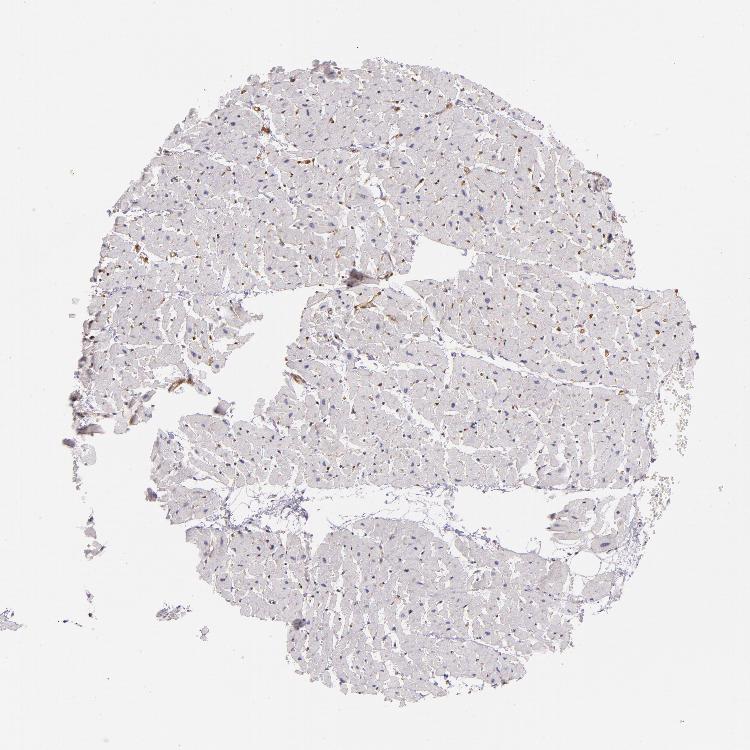

HEART MUSCLE - Antibody stainingi

Antibody staining in the annotated cell types in the current human tissue is reported as not detected, low, medium, or high, based on conventional immunohistochemistry profiling in selected tissues. This score is based on the combination of the staining intensity and fraction of stained cells.

Each image is clickable and will lead to virtual microscopy that enables deeper exploration of all samples and also displays staining intensity scores, fraction scores and subcellular localization as well as patient and tissue information for each sample.

Antibody HPA004748Antibody CAB002006

Cardiomyocytes Not detectedNot detected